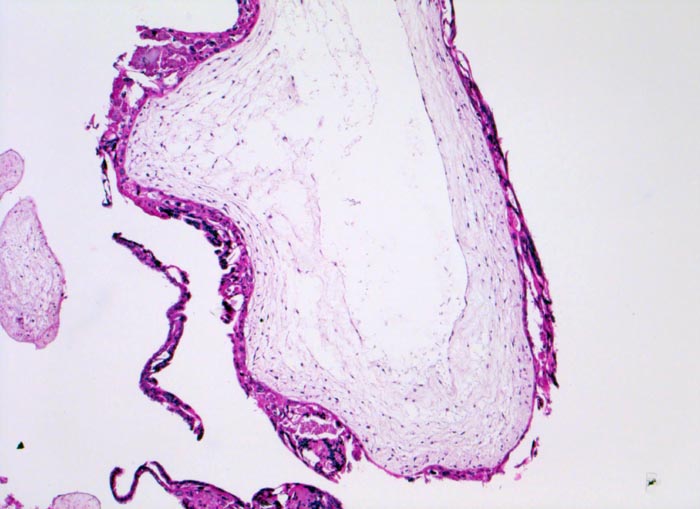

Makroskopisch ist die Plazenta deutlich grösser als erwartet für das Schwangerschaftsalter. Sie ist diffus von bis 2cm grossen Zottenblasen durchsetzt, welche nach Kollaps jedoch der makroskopischen Entdeckung entgehen können. Beim Aufschwemmen in Flüssigkeit entfalten sich die Blasen wieder. Mikroskopisch sind die Zotten aufgrund einer grobblasigen pseudozystischen Hohlraumbildung im Zottenstroma überwiegend grosskalibrig. Im Zottenstroma sind nur ganz vereinzelt Kapillaren nachweisbar. Im Gegensatz zu hydropisch geschwollenen Zotten im Sinne eines Regressionsphänomens zeigen die Zotten bei Blasenmole zusätzlich eine zirkumferentielle Hyperplasie von Synzytio- und Zytotrophoblast mit fakultativer Zellatypie. Bei herdförmiger Mole (> 3725) sind diese Veränderungen nur in einem Teil der Plazentarzotten ausgeprägt.

• Stark vergrösserte und verplumpte Plazentarzotten.

• Hydropisch umgewandeltes Zottenstroma ohne Gefässe mit Ausbildung von pseudozystischen Hohlräumen (Blasen)

• Trophoblastinklusionen und Kerntrümmer im Zottenstroma.

• Überschiessend proliferiertes Trophoblastepithel, teils in der gesamten Zirkumferenz der Zotten mit deutlichen Kernatypien. Kein Embryo.